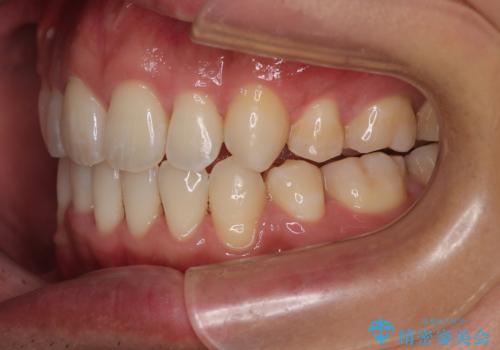

歯をすべて並べようとすると口元がさらに前に出てしまうため、上下左右の第一小臼歯を抜歯してスペースを確保し、デコボコと突出感の両方を改善する治療計画を立てました。

舌を前に押し出す癖(舌突出癖)があり、後戻りやオープンバイトの再発防止のため、MFT(口腔筋機能療法)も併用しています。